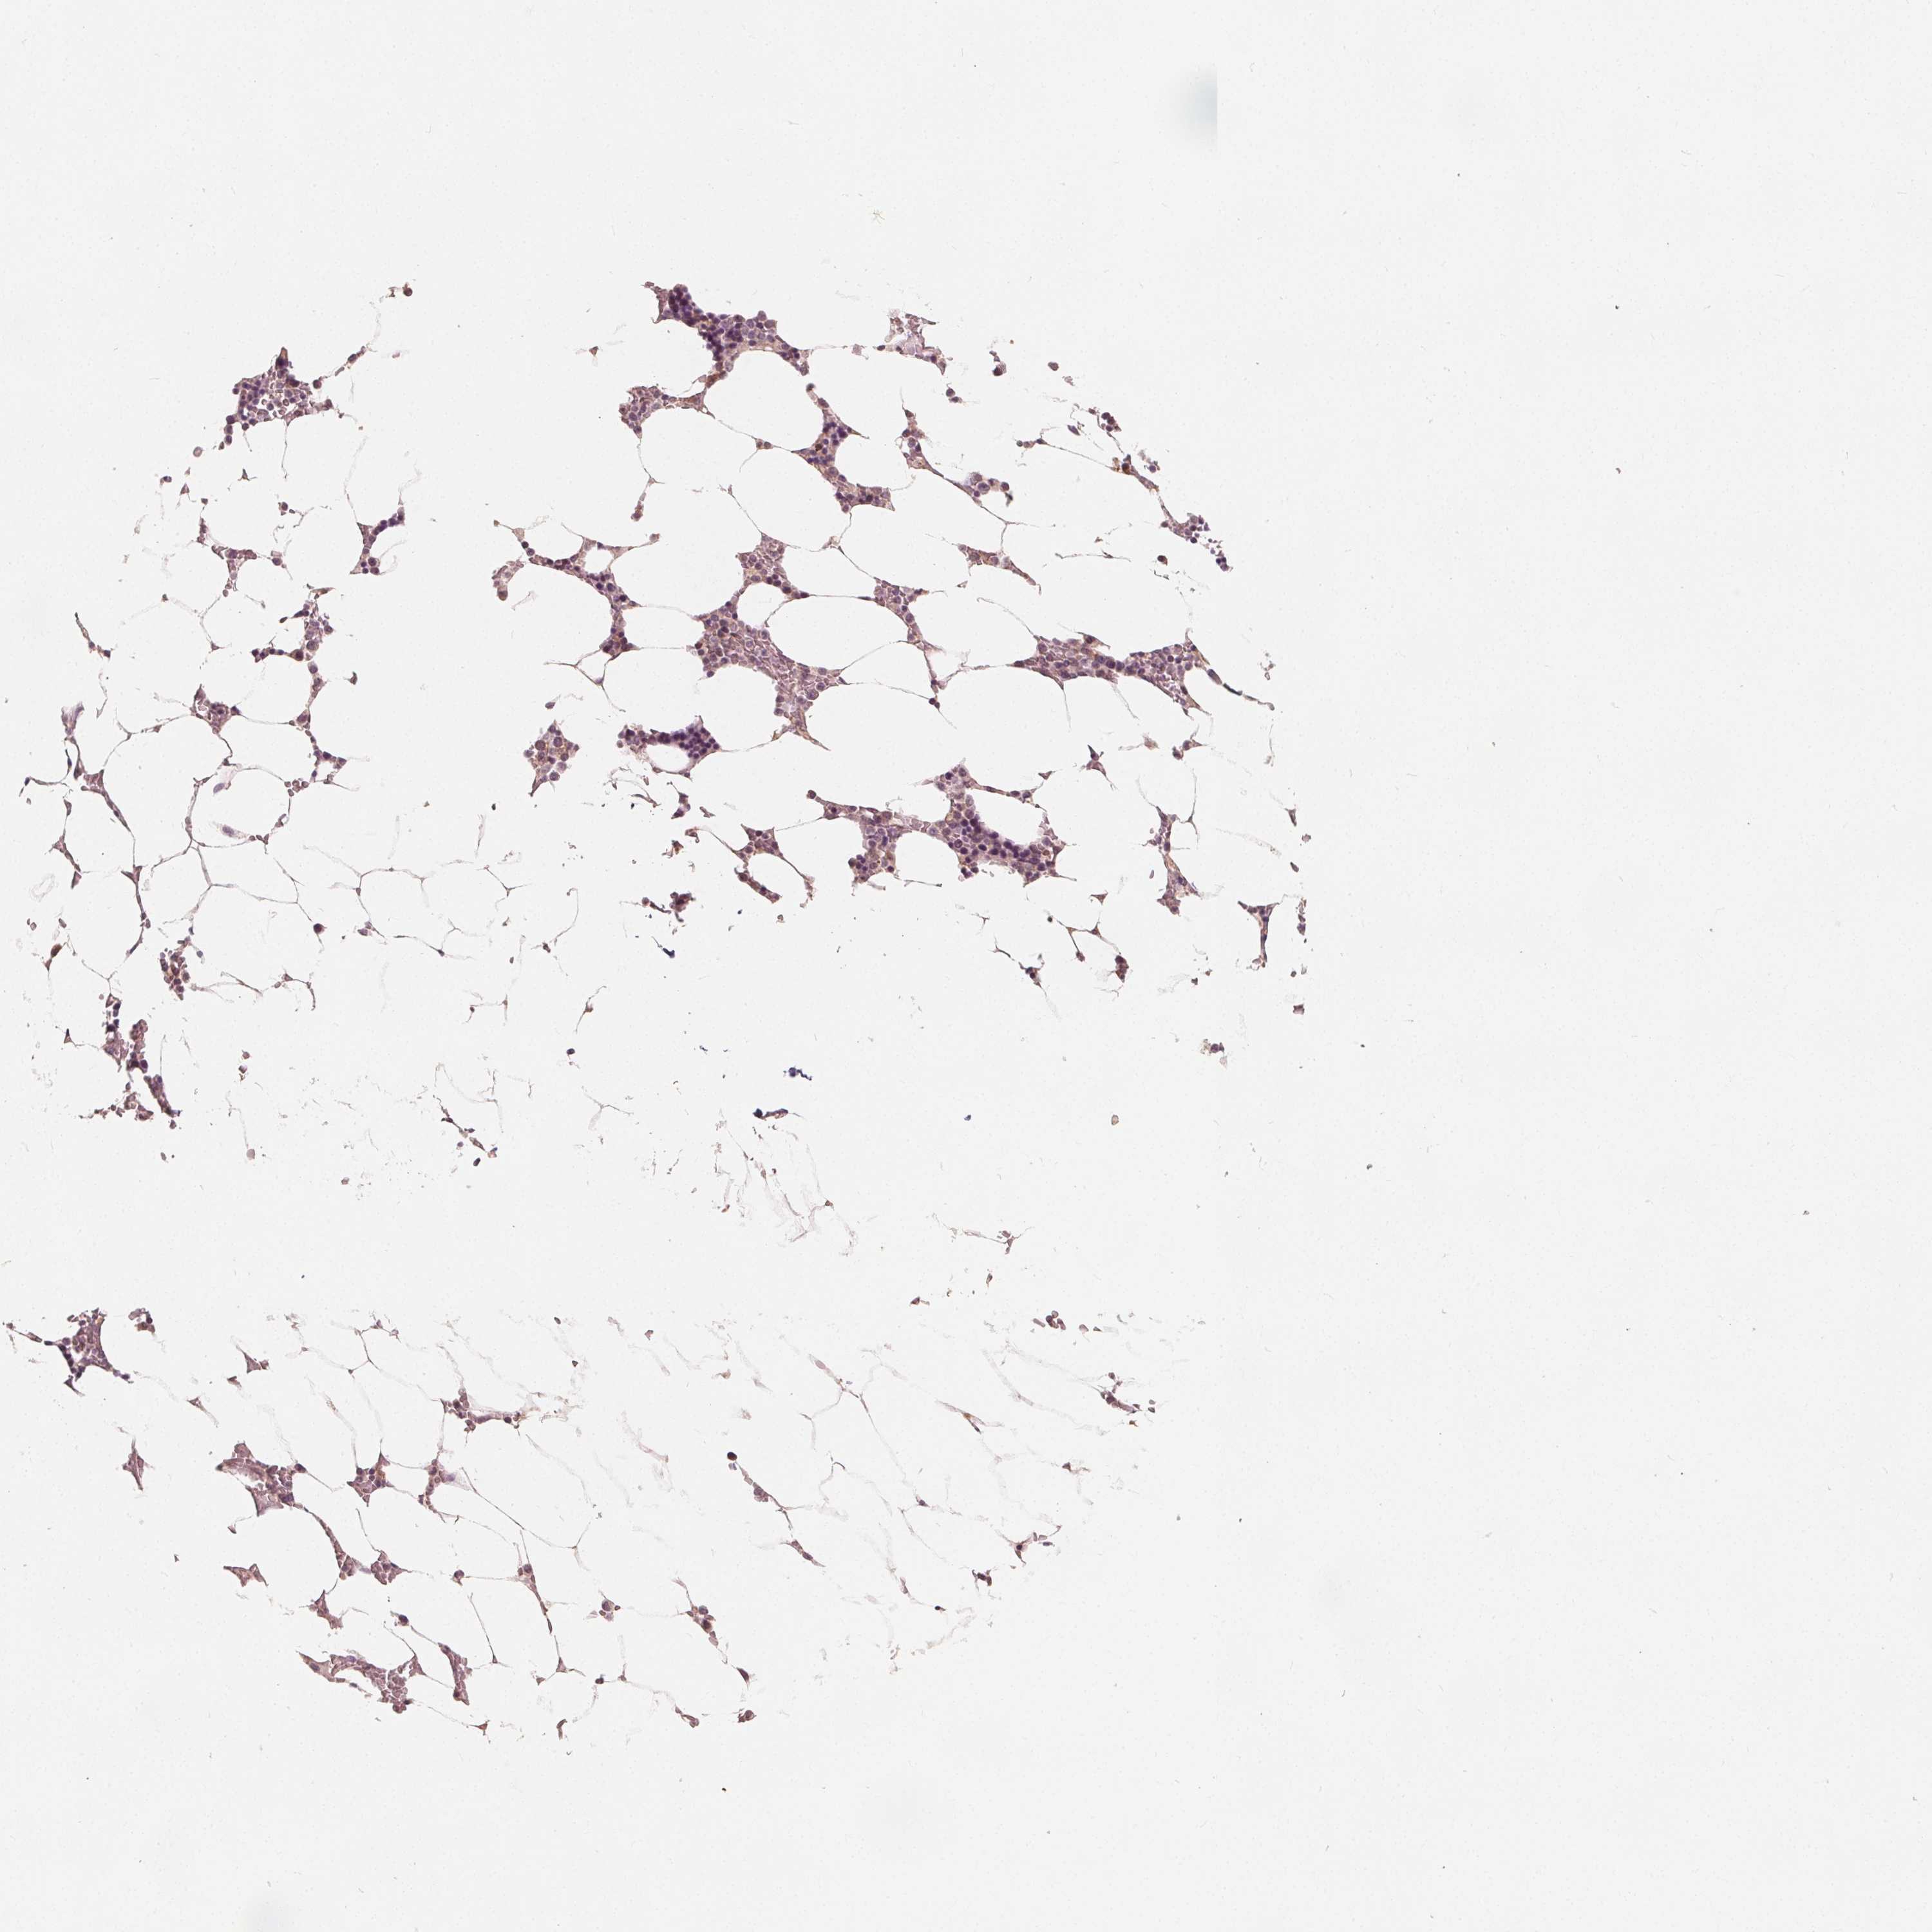

SNX12